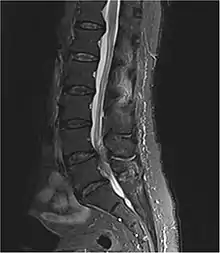

Diagnosis is usually confirmed by an MRI scan or CT scan, depending on availability.[14] Bladder scanning and loss of catheter sensation can also be used to diagnose an onset of cauda equina syndrome and can aid diagnosis before MRI scanning. Early surgery in acute onset of severe cases has been reported to be important.[14]